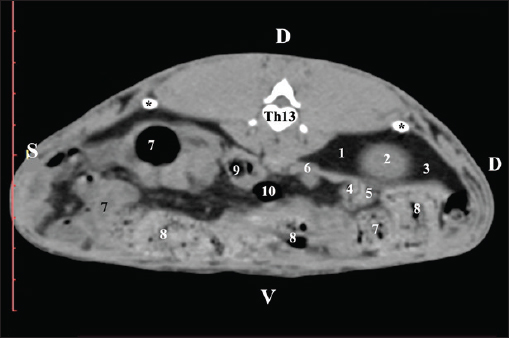

CT anatomical study at the Th13 level was used to define the right kidney zones. The medulla renalis was found as a hyperattenuated soft tissue with peripheral linear and wavy margins that reached the relatively hypoattenuated renal cortex. The most peripheral structure was the capsula adiposa, characterized by hyperattenuated soft tissue and uniform relief. The hyperattenuated aorta abdominalis, v. cava caudalis, and a. renalis appeared medially to the right kidney (Fig. 14).

Fig. 14. Post-contrast computed tomography (CT) anatomical scan of regio abdominis cranialis at the Th13 level. (1) Lobus hepatis dexter; (2) ren dexter; (3) lobus caudatus (processus caudatus); (4) aorta abdominalis; (5) v. cava caudalis; (6) a. renalis; (7) ureter; (8) capsula adiposa (capsula fibrosa); (9) pars descendens of the duodenum; (10) ileum; (11) cecum; (12) colon ascendens; (13) colon transversum; (14) colon descendens; (15) gl. adrenalis dextra; (black arrowhead) XIII rib; (*) cortex renalis; (**) medulla renalis.